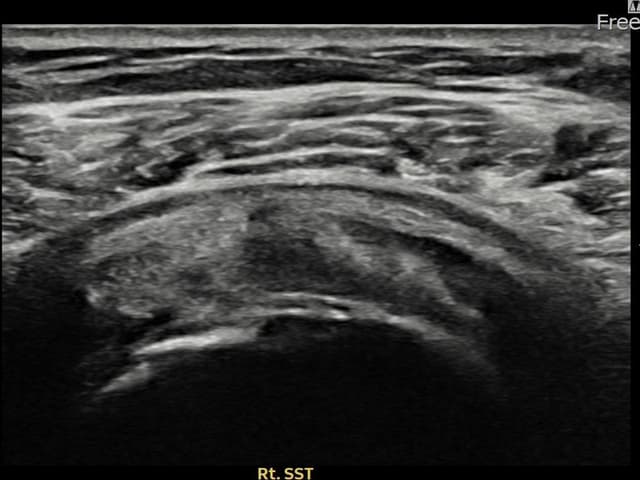

[촬영시기:22.09.19~22.12.09]

[어깨인대 축소봉합술] 우측 어깨 통증과 팔을 특정 각도로 올릴 때 심해지는 충돌 증상으로 내원하셨습니다.